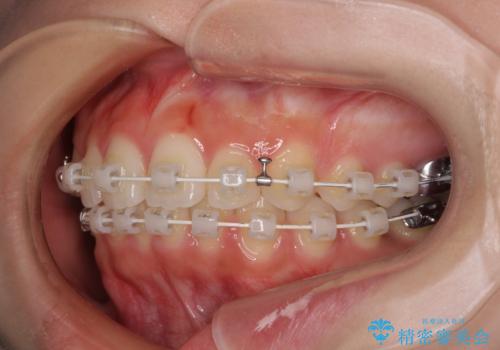

- 矯正装置

- 審美装置

上顎前歯の突出感は、上顎全体が前方に位置していることが原因であったため、補助装置により上顎全体を後方に移動させることとしました。

後方移動と同時上下歯列をワイヤー装置にて整え、奥歯の欠損部には矯正治療の途中でインプランを埋入していくこととしました。